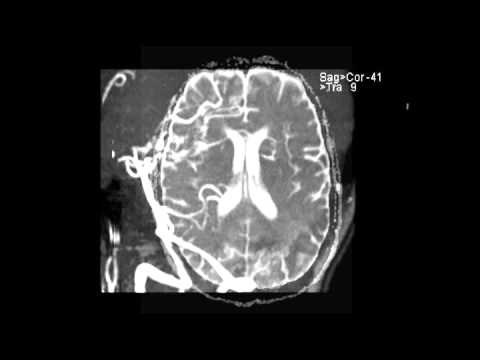

VZV Vasculitis